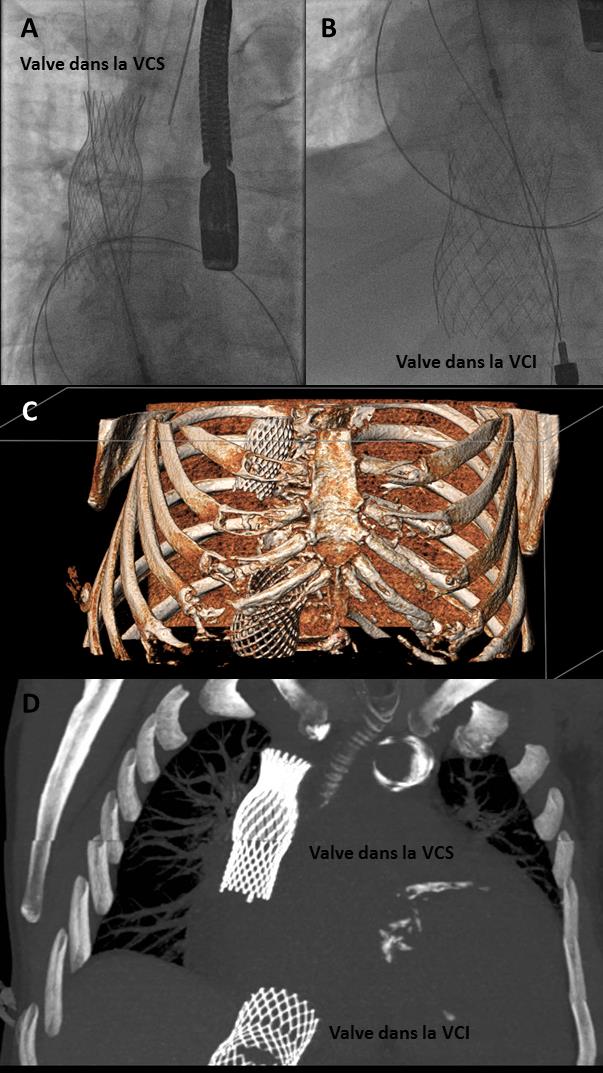

Procédure d’implantations des valves dans les veines caves supérieure (VCS) (A) et inférieure (VCI) (B). (C) et (D): Visualisation du dispositif TricValve après implantation au scanner

La procédure a consisté, après une ponction veineuse fémorale, en l’implantation de deux stents valvés à armature autoexpansible au niveau des deux veines caves par voie percutanée sous contrôle angiographique et échographique. Elle a permis de faire disparaître les œdèmes du patient qui a pu sortir rapidement du service de cardiologie de l’hôpital Henri-Mondor AP-HP.